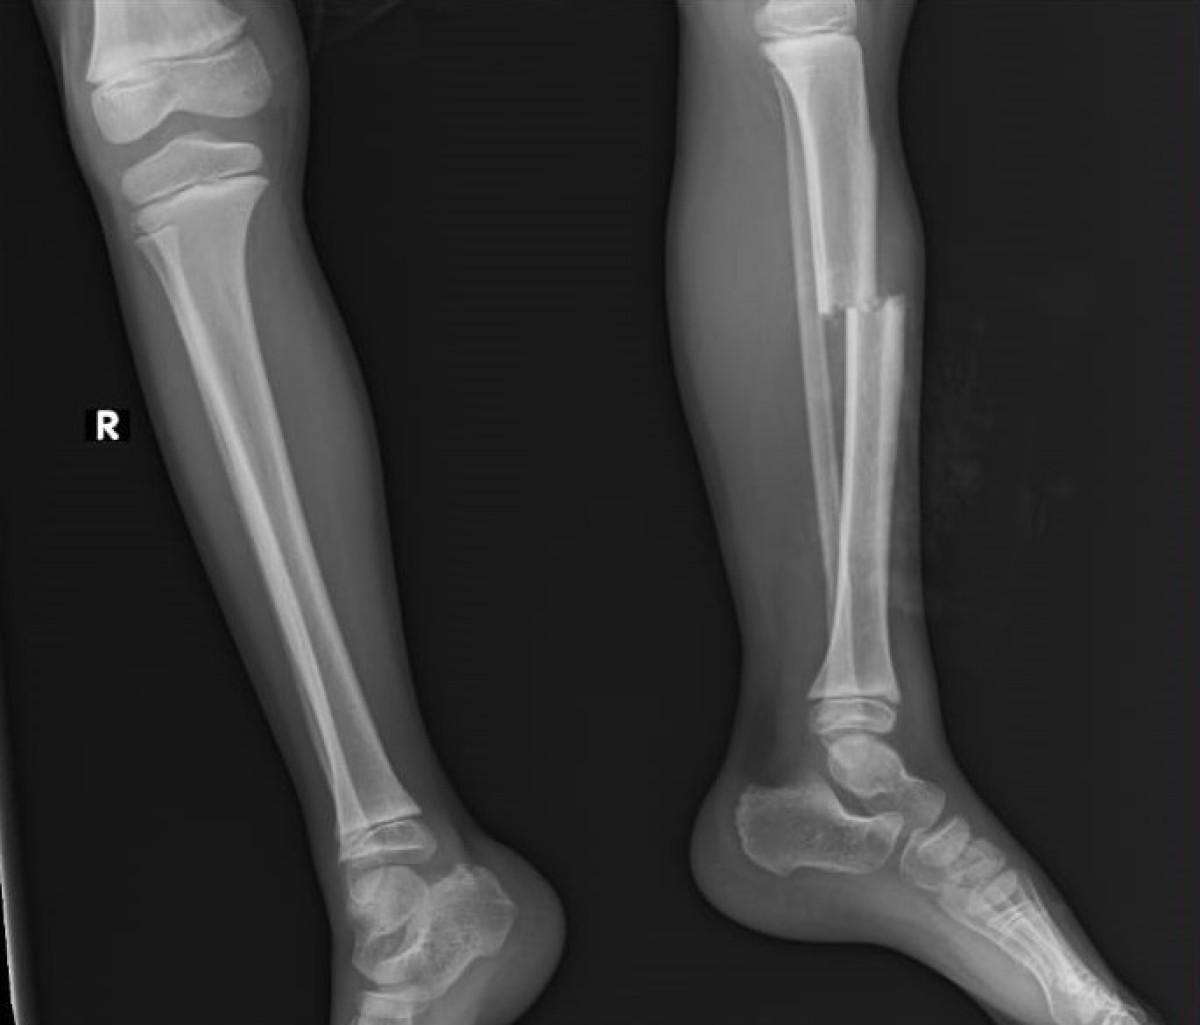

Sol bacak kaval kemiği kırılan, kafa ve vücudunun çeşitli noktalarında kesiler oluşan küçük Eymen, Kepez Devlet Hastanesi'nde tedavi altına alındı.